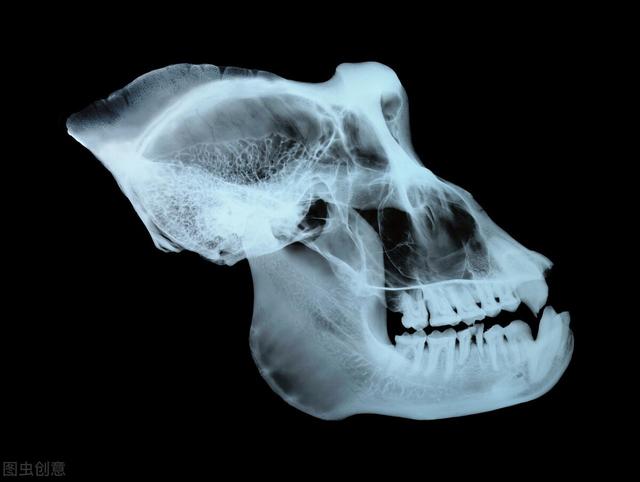

颌骨囊肿多发于青壮年时期,正常情形 下病发前没有什么特殊的征兆,部门患者可能会泛起压痛或是稍微 的自主性疼痛;在逐步发育后,颌骨内含有液体的囊肿会逐步 变大,直至膨胀到破损 颌骨,不实时治疗就可导致患者面部畸形。